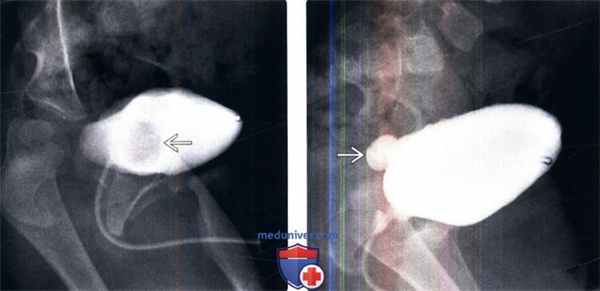

(Слева) МЦУГ в прямой косой проекции: у младенца мужского пола с анамнезом инфекции мочевыделительных путей определяется округлый дефект наполнения мочевого пузыря с гладкой поверхностью. Эти признаки характерны для уретероцеле.

(Справа) После дальнейшего растяжения мочевого пузыря уретероцеле вывернулось наружу из просвета мочевого пузыря. Выворот уретероцеле можно ошибочно принять за дивертикул мочевого пузыря.

• Микционная цистоуретрография(МЦУГ):

о Гладкое рентгенонегативное образование в мочевом пузыре

о Уретероцеле может временно выворачиваться при мочеиспускании и имитировать дивертикул («выворот уретероцеле»)